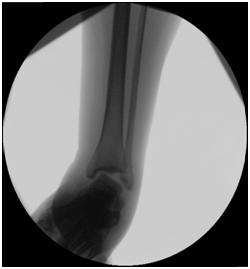

Treatment Management began with stabilization of the patient’s general condition, and later definite treatment on 2nd stages. 1st stage: Patient went for decompression spine surgery and examination under anesthesia (EUA) of the right ankle which demonstrated medial and lateral ligament complex instability as evident by a positive anterior drawer test (Figure 3), a posterior drawer test (Figure 4) and a positive varus and valgus stress tests with intact syndesmosis clinically (Figure 5 & 6). Because of the local swelling, the patient was put in a cast. 2nd stage: 5 days later, when the swelling subsided, patient underwent open reduction internal fixation of the right calcaneus fracture and repair of the medial and lateral ligament complex tears.

Figure 3 Anterior drawer test: an anteriorly directed force is applied to the heel while supporting the leg.

Figure 4  Posterior drawer test: a posteriorly directed force is applied to the foot while supporting the leg.